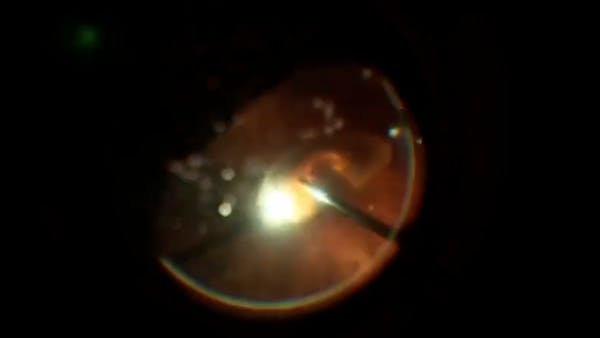

Surgery for a Dense Cataract

Brenton D. Finklea, MD